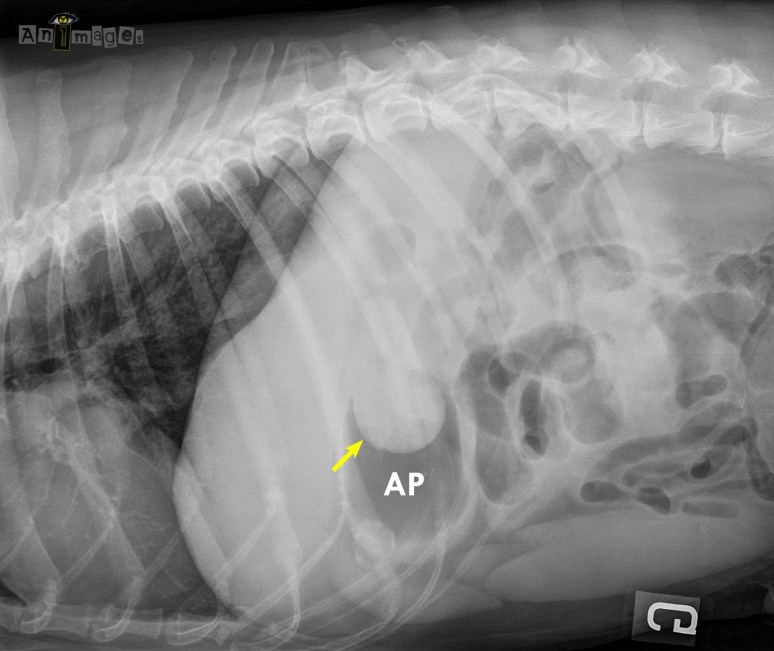

Les images ci-bas ont été prises chez un jeune chien de grande race présenté pour des vomissements persistants et une douleur abdominale. Qu’en pensez-vous ?

L’estomac contient du liquide et du gaz, sans distension anormale. Plusieurs segments intestinaux sont irréguliers avec présence de quelques replis et d’un contenu anormal qui pourrait coller avec un corps étranger linéaire. On serait tenté de recommander une échographie pour le confirmer, non ? Mais si on prenait une latérale gauche ?

Maintenant que l’air dans la lumière gastrique se retrouve dans l’antre pylorique (AP, située en hauteur sur cette projection), on peut clairement identifier une opacité de tissu mou arrondie (flèche) qui se prolonge vraisemblablement dans le canal pylorique sous forme de corps étranger linéaire. L’animation ci-bas illustre bien l’impact du décubitus sur le déplacement du liquide et du gaz dans la lumière gastrique, d’un point de vue crânial (i.e. faisant face à la tête d’un chien couché sur le côté). En décubitus droit, le corps étranger logé dans l’antre pylorique (AP) se retrouve entouré de liquide dont l’opacité radiographique est sensiblement la même, limitant du coup sa détection. En décubitus gauche, l’air se déplace dans l’antre pylorique maintenant placée vers le haut, mettant bien en relief le corps étranger. E= oesophage, F= fundus, C= corps de l’estomac.

Ce concept pourrait justifier l’ajout d’une autre latérale lors de suspicion de corps étranger gastrique ou duodénal ! À bon entendeur, salut ! 😉